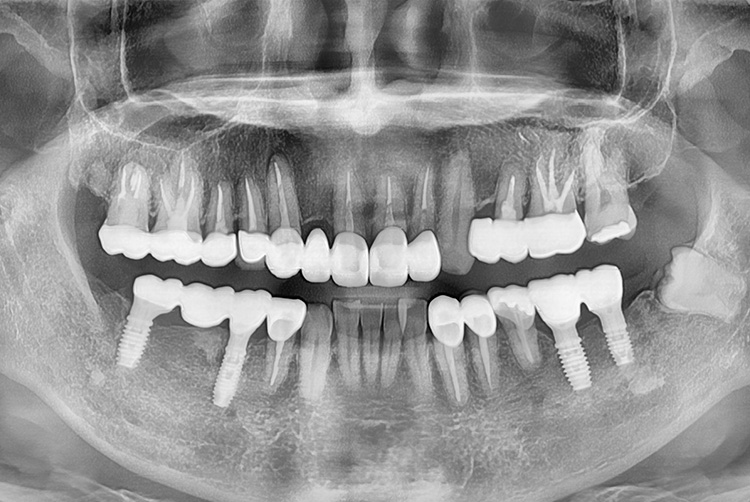

[임플란트] 임플란트

치료후 : 2022-03-12

세종치과는 많은 환자와 다양한 케이스를 바탕으로 항상 편안한 임플란트 수술을 제공하고자 노력하고,

오래동안 튼튼히 쓸 수 있는 임플란트 수술을 가장 큰 목표로 삼고 있습니다